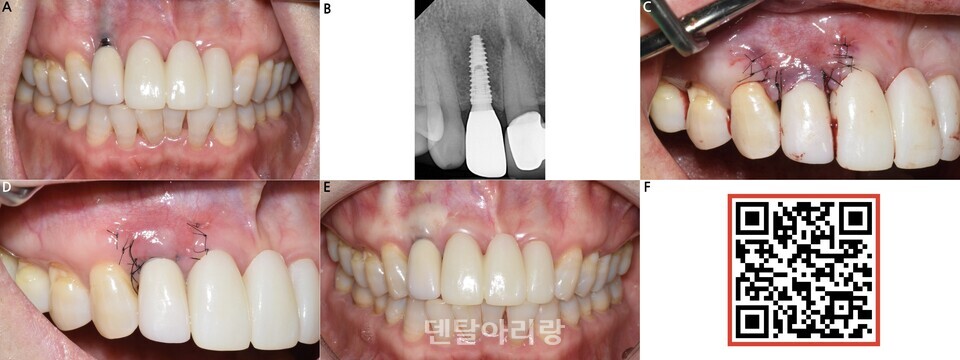

△ 그림 2. 임플란트 주위염에 이환된 부위에 염증 치료 후 이종 콜라겐 연조직 대체재를 이식하여 임플란트 주위 연조직 환경을 개선한 증례. (a) #21i 임플란트에 임플란트 주위염으로 인해 순측 점막 발적과 더불어 순측 중앙부에 누공이 관찰되는 모습. (b) 전층 판막 거상 후 관찰되는 임플란트 주위 병적 골흡수. (c) 골흡수 부위에 연조직 대체재를 적용한 모습. (d) 전층 판막을 제 위치로 봉합한 모습. (e) 술 후 2개월 후 모습. (f) 술 후 6개월 후 건강한 각화 점막에 의해 피개된 상태로 유지 중인 #21i 임플란트의 모습.